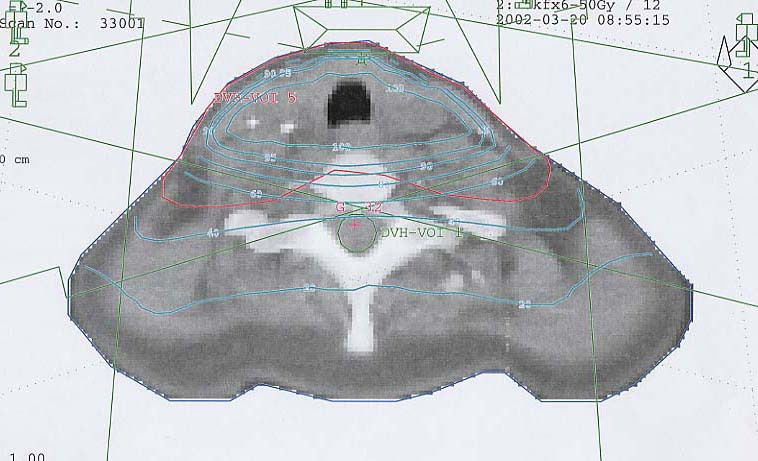

Schilddrüsenkarzinom: Bestrahlungsplan